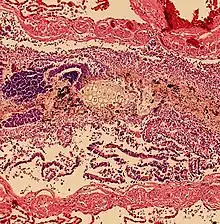

Death

Histopathology of aspiration, taken from an autopsy, showing plant-like cells in a bronchiole. However, alveoli were clear, indicating a finding secondary to cardiopulmonary resuscitation rather than a primary cause of death.